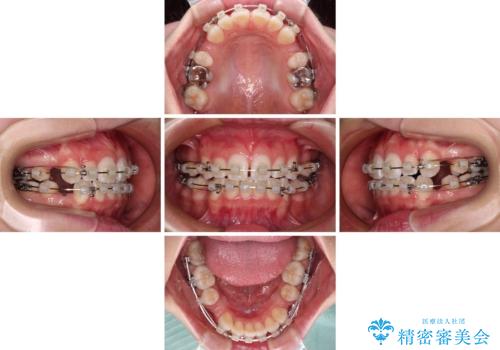

- クリアブラケット

- 1年6ヶ月

- 10-30回